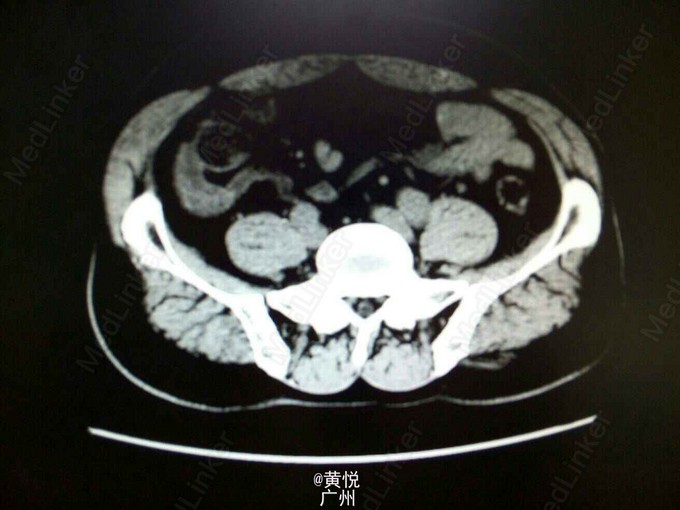

查体:生命体征平稳,屈曲体位,心肺无特殊,腹平软,右下腹麦氏点有压痛以及反跳痛,无腹部包块,双肾叩击痛(—)。辅助检查:血常规提示WBC 1.3*10^9;中性粒细胞 6.7*10^9,中性粒细胞比值正常;血生化未见异常。腹平片提示:小肠少许积气,考虑肠郁张;腹部CT检查提示结肠局部肠壁增厚并周围淋巴结增大,建议进一步检查,考虑右肾囊肿。